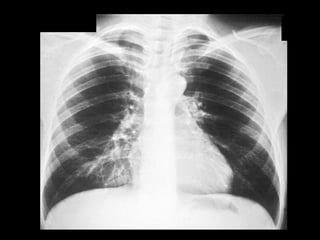

Infiltrado en alasde mariposa ó de murciélago, por edema pulmonar . Líneas B de Kerley .

Existe también cefalización de flujo. También llamado redistribución de flujo.